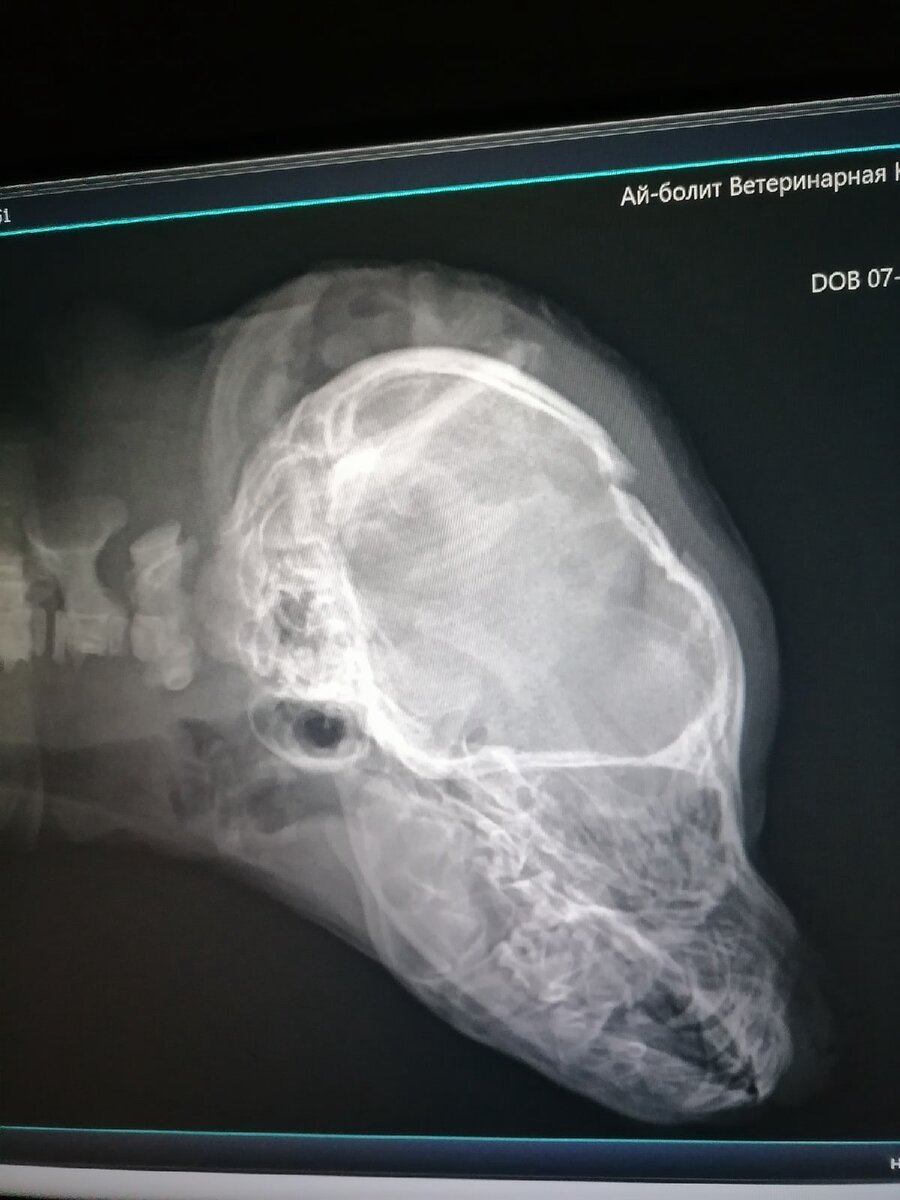

Снова травма головы, на этот раз видимо покус собакой...

Щенок, примерно 1.5 месяца, перелом основания черепа, состояние тяжелое.

Сейчас в клинике, в барокамере.